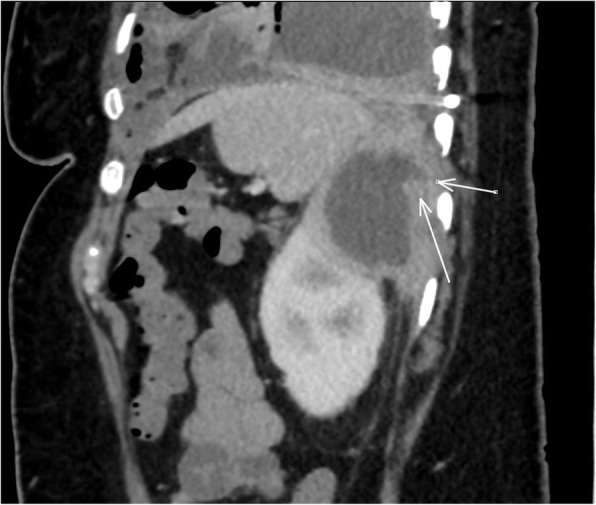

Fig. 2.

Computed Tomography results showing a sagittal cross section of the patient’s abdomen with the white arrows indicating the renal cyst and tract extending posteriorly to the diaphragm